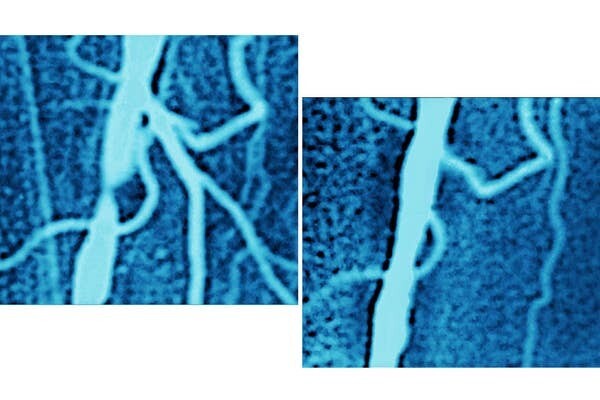

25. Подвздошная артерия пациента до и после процедуры ангиопластики